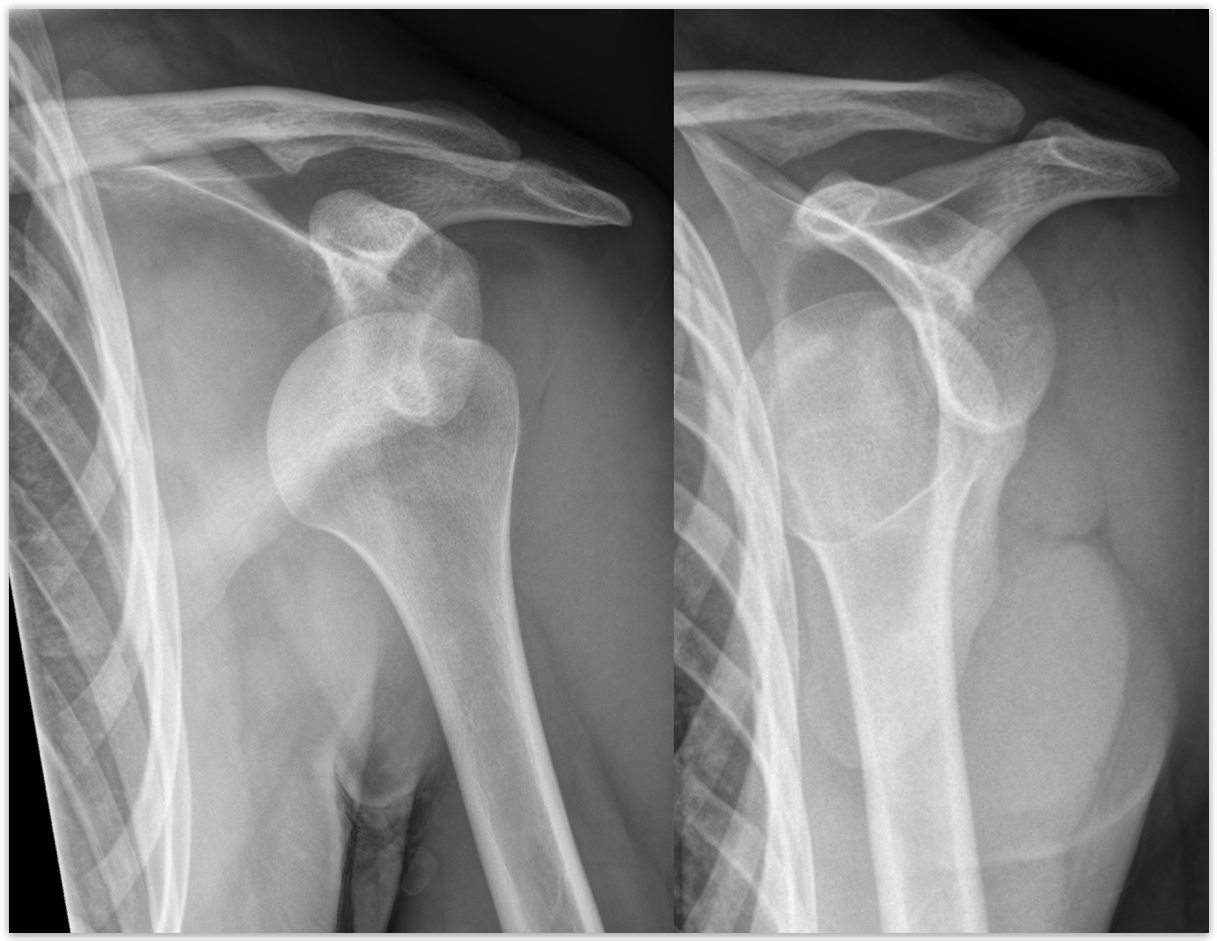

how does a GH Subluxations/Dislocations occur?

force on shoulder, can have anterior (most common), posterior, and inferior (rare) dislocations

GH Subluxations/Dislocations symptoms

A sublux will have pain, limited ROM, while a dislocation will have a deformity, pain, and no ROM

GH Subluxations/Dislocations treatment

If trained, reduce it and ship; if not, splint and ship

first time dislocation = always suspect a fracture

chronic inj. = may brace to reduce the chance, as the labrum is torn

person needs to keep up with a rehab plan, as the dynamic muscles are the best thing to keep the GH head in